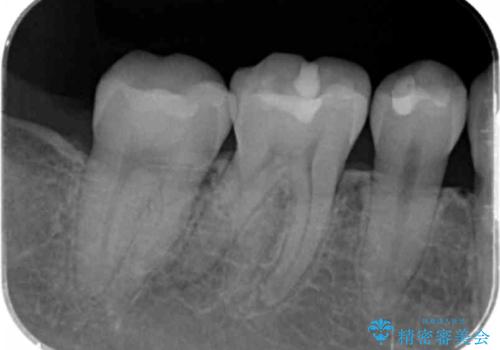

奥歯が欠けた セラミックインレーでの修復後、ナイトガード装着

- 右下の奥歯が欠けたとのことで来院されました。

欠けた部分にはセラミックインレーで修復処置を行い、今後の破折リスクを抑えるためにナイトガードを製作していきます。

- 右下7 セラミックインレー 77,000円/ナイトガード 33,000円費用は治療当時の料金となります